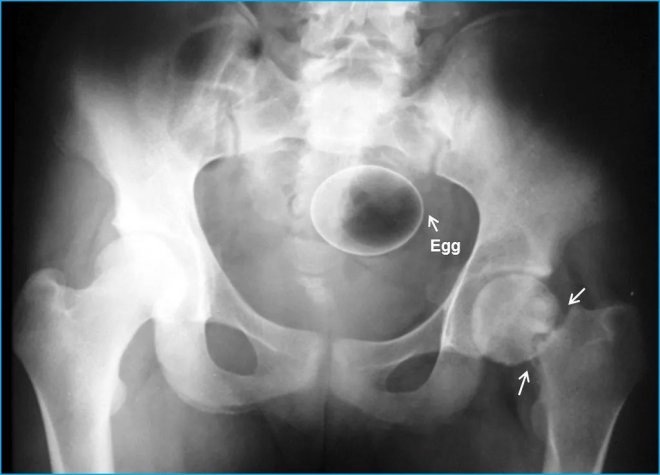

蛋

從體積來看應該是雞蛋,患者同時還有脖子骨折症狀